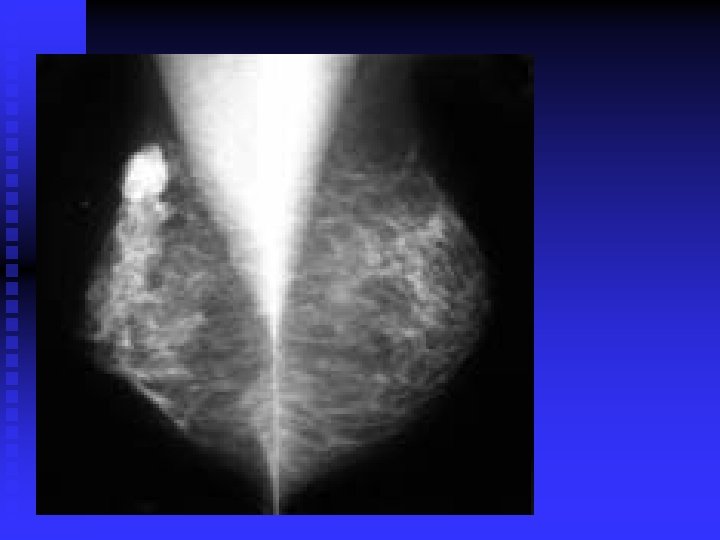

28 -year-old woman 4 months postpartum and not breast-feeding. The right breast contains a

28 -year-old woman 4 months postpartum and not breast-feeding. The right breast contains a large mass (arrow) palpable on physical examination. The left breast contains two smaller nonpalpable masses (arrows) with microcalcifications. All three lesions were breast cancers.